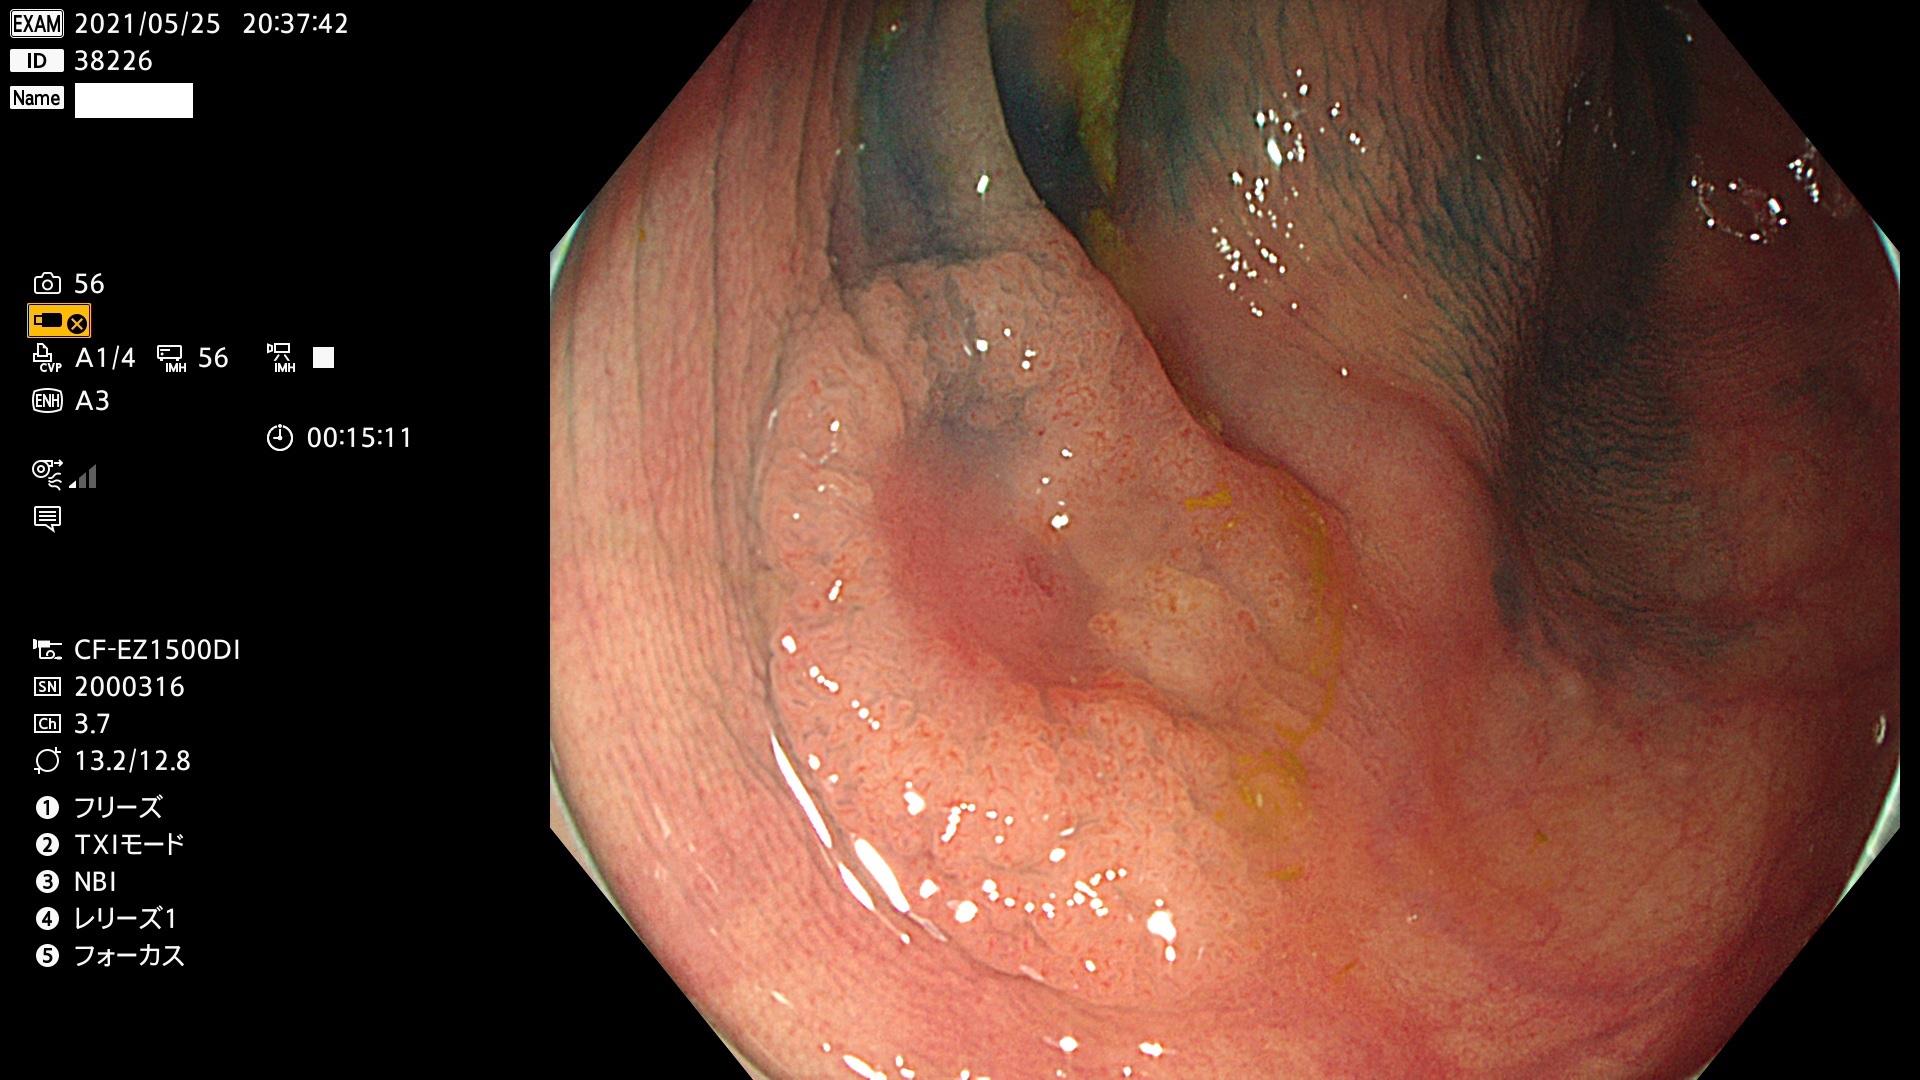

発見困難で危険性の高い平坦型病変(上記100名より抽出)